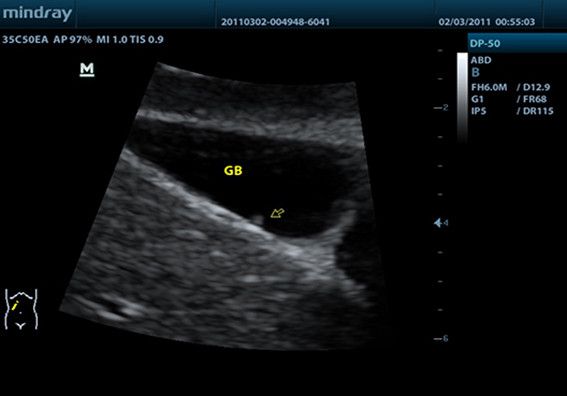

Клинические изображения

- Абдоминальные исследования